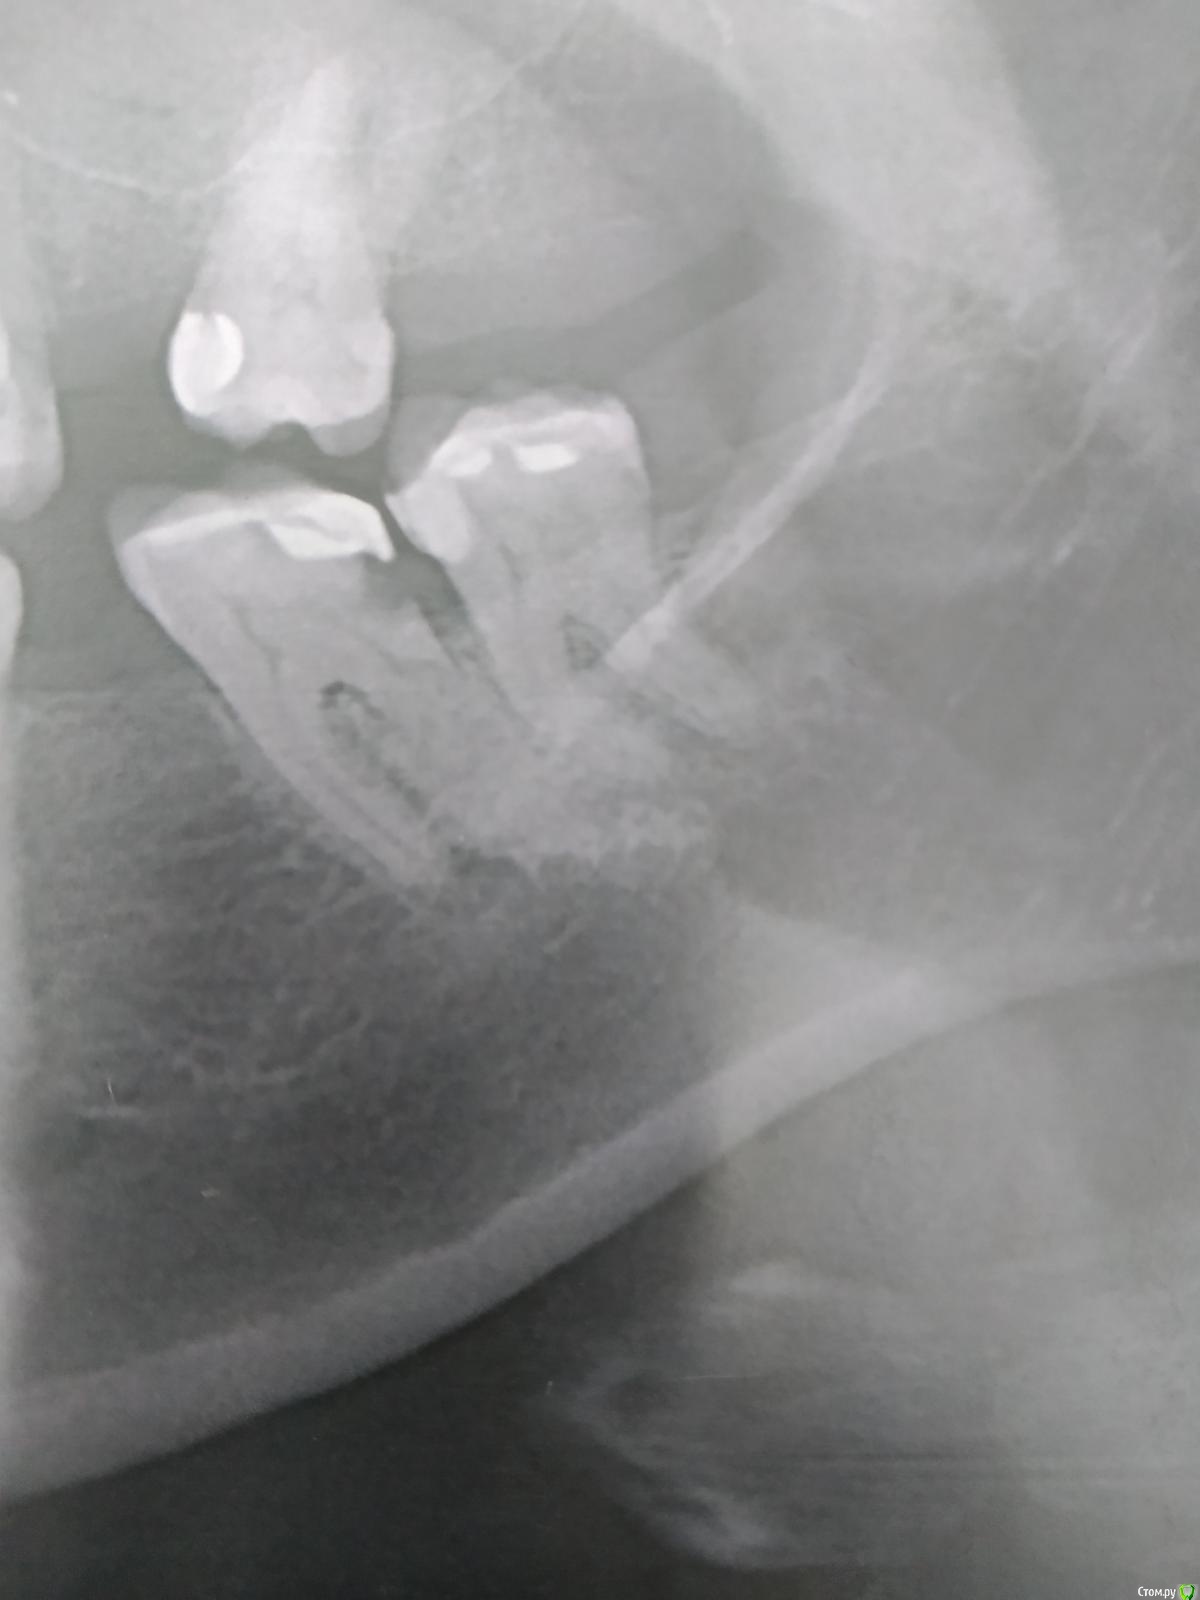

shishok Опубликовано 9 ноября, 2020 Поделиться Опубликовано 9 ноября, 2020 Уважаемые коллеги!Что за образование на РГ в области дистального корня 37?Не беспокоит.КТ нет. Ссылка на комментарий

Carioznik Опубликовано 9 ноября, 2020 Поделиться Опубликовано 9 ноября, 2020 Уважаемые коллеги!Что за образование на РГ в области дистального корня 37?Не беспокоит.КТ нет.Гиперцементоз?заместительная резорбция? Ссылка на комментарий